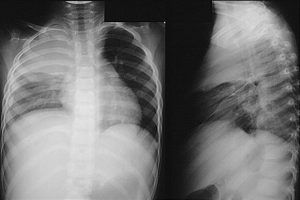

Giãn phế quản là một bệnh lý thuộc chuyên khoa hô hấp. Bệnh gây tổn thương trực tiếp đến phế quản, đường dẫn khí trong phổi, có thể dẫn tới nhiều biến chứng đáng lo ngại. Hãy cùng Docosan tìm hiểu về triệu chứng và các cách điều trị giãn phế quản trong y học […]